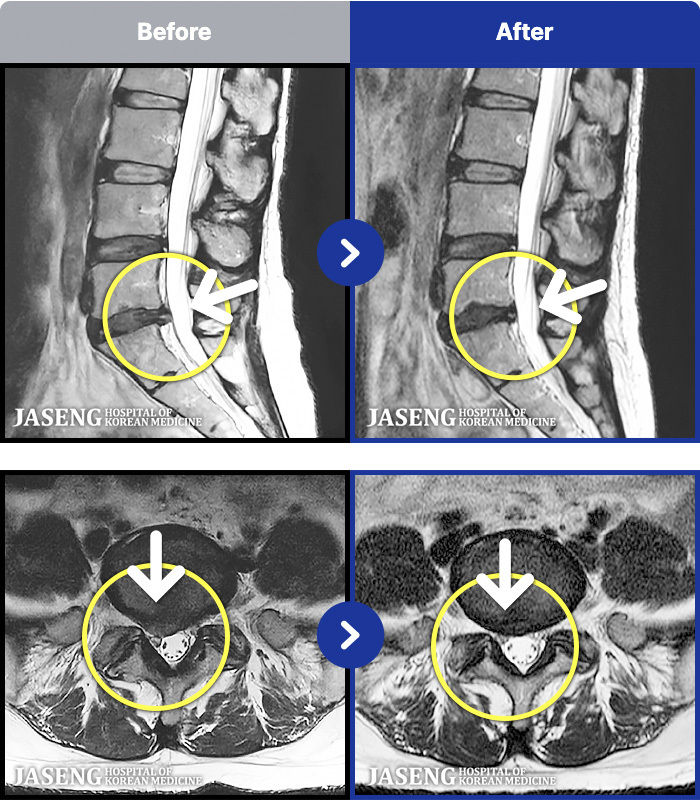

- MRI ġ

MRI ġ

191 MRI ũ ʸ Ȯϼ.

[Կñ:25.08.06~26.02.24]

[_㸮ũ] ٸ 㸮 ȹٷ , Բ 㸮 ־ ߴ.